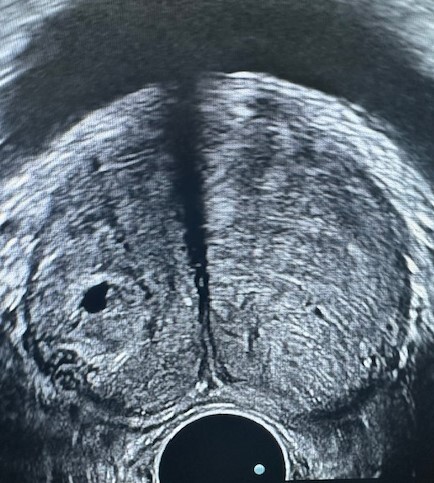

— УЗИ мочевой системы и простаты,